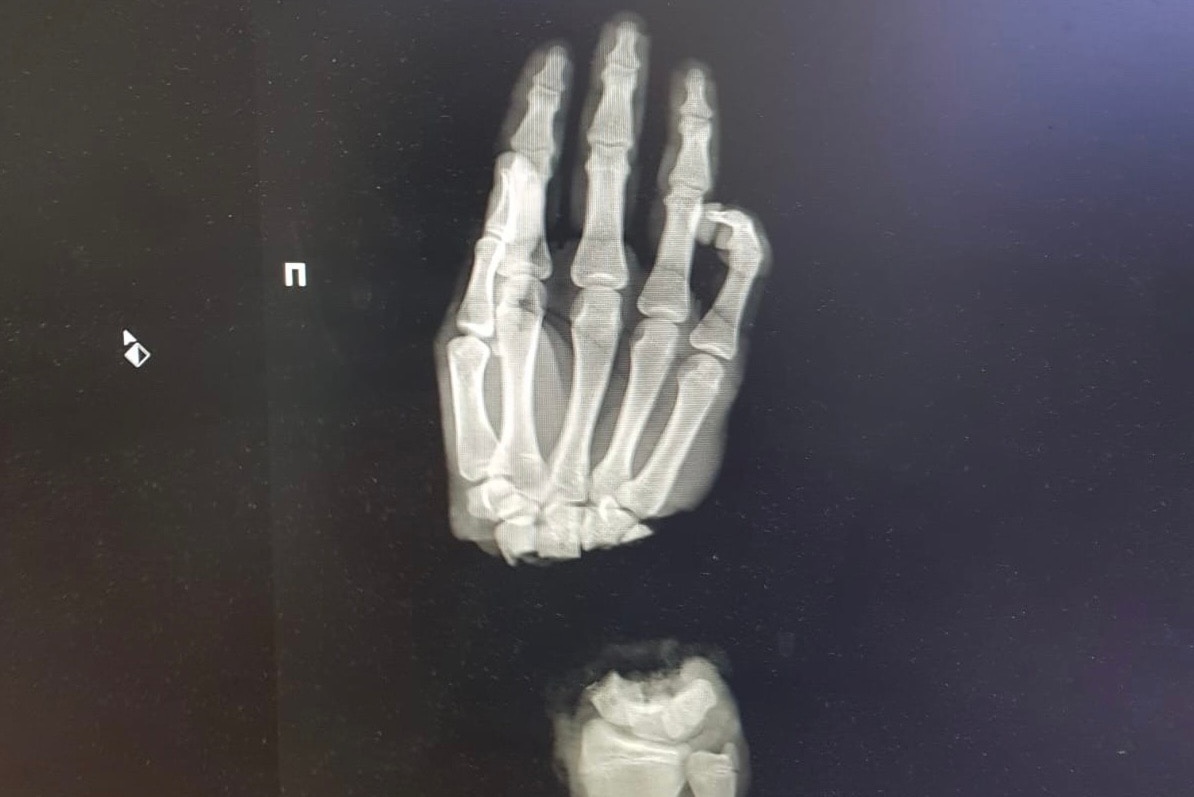

1 марта в Нижний Новгород из Коврова привезли 16-летнего парня, который колол дрова и отрубил себе топором кисть. В тот же вечером врачи клиники провели операцию по реимплантации конечности. Сейчас состояние пациента стабильное, кровоснабжение кисти восстановлено, однако молодому человек предстоит еще несколько операций, чтобы максимально восстановить функциональность руки.